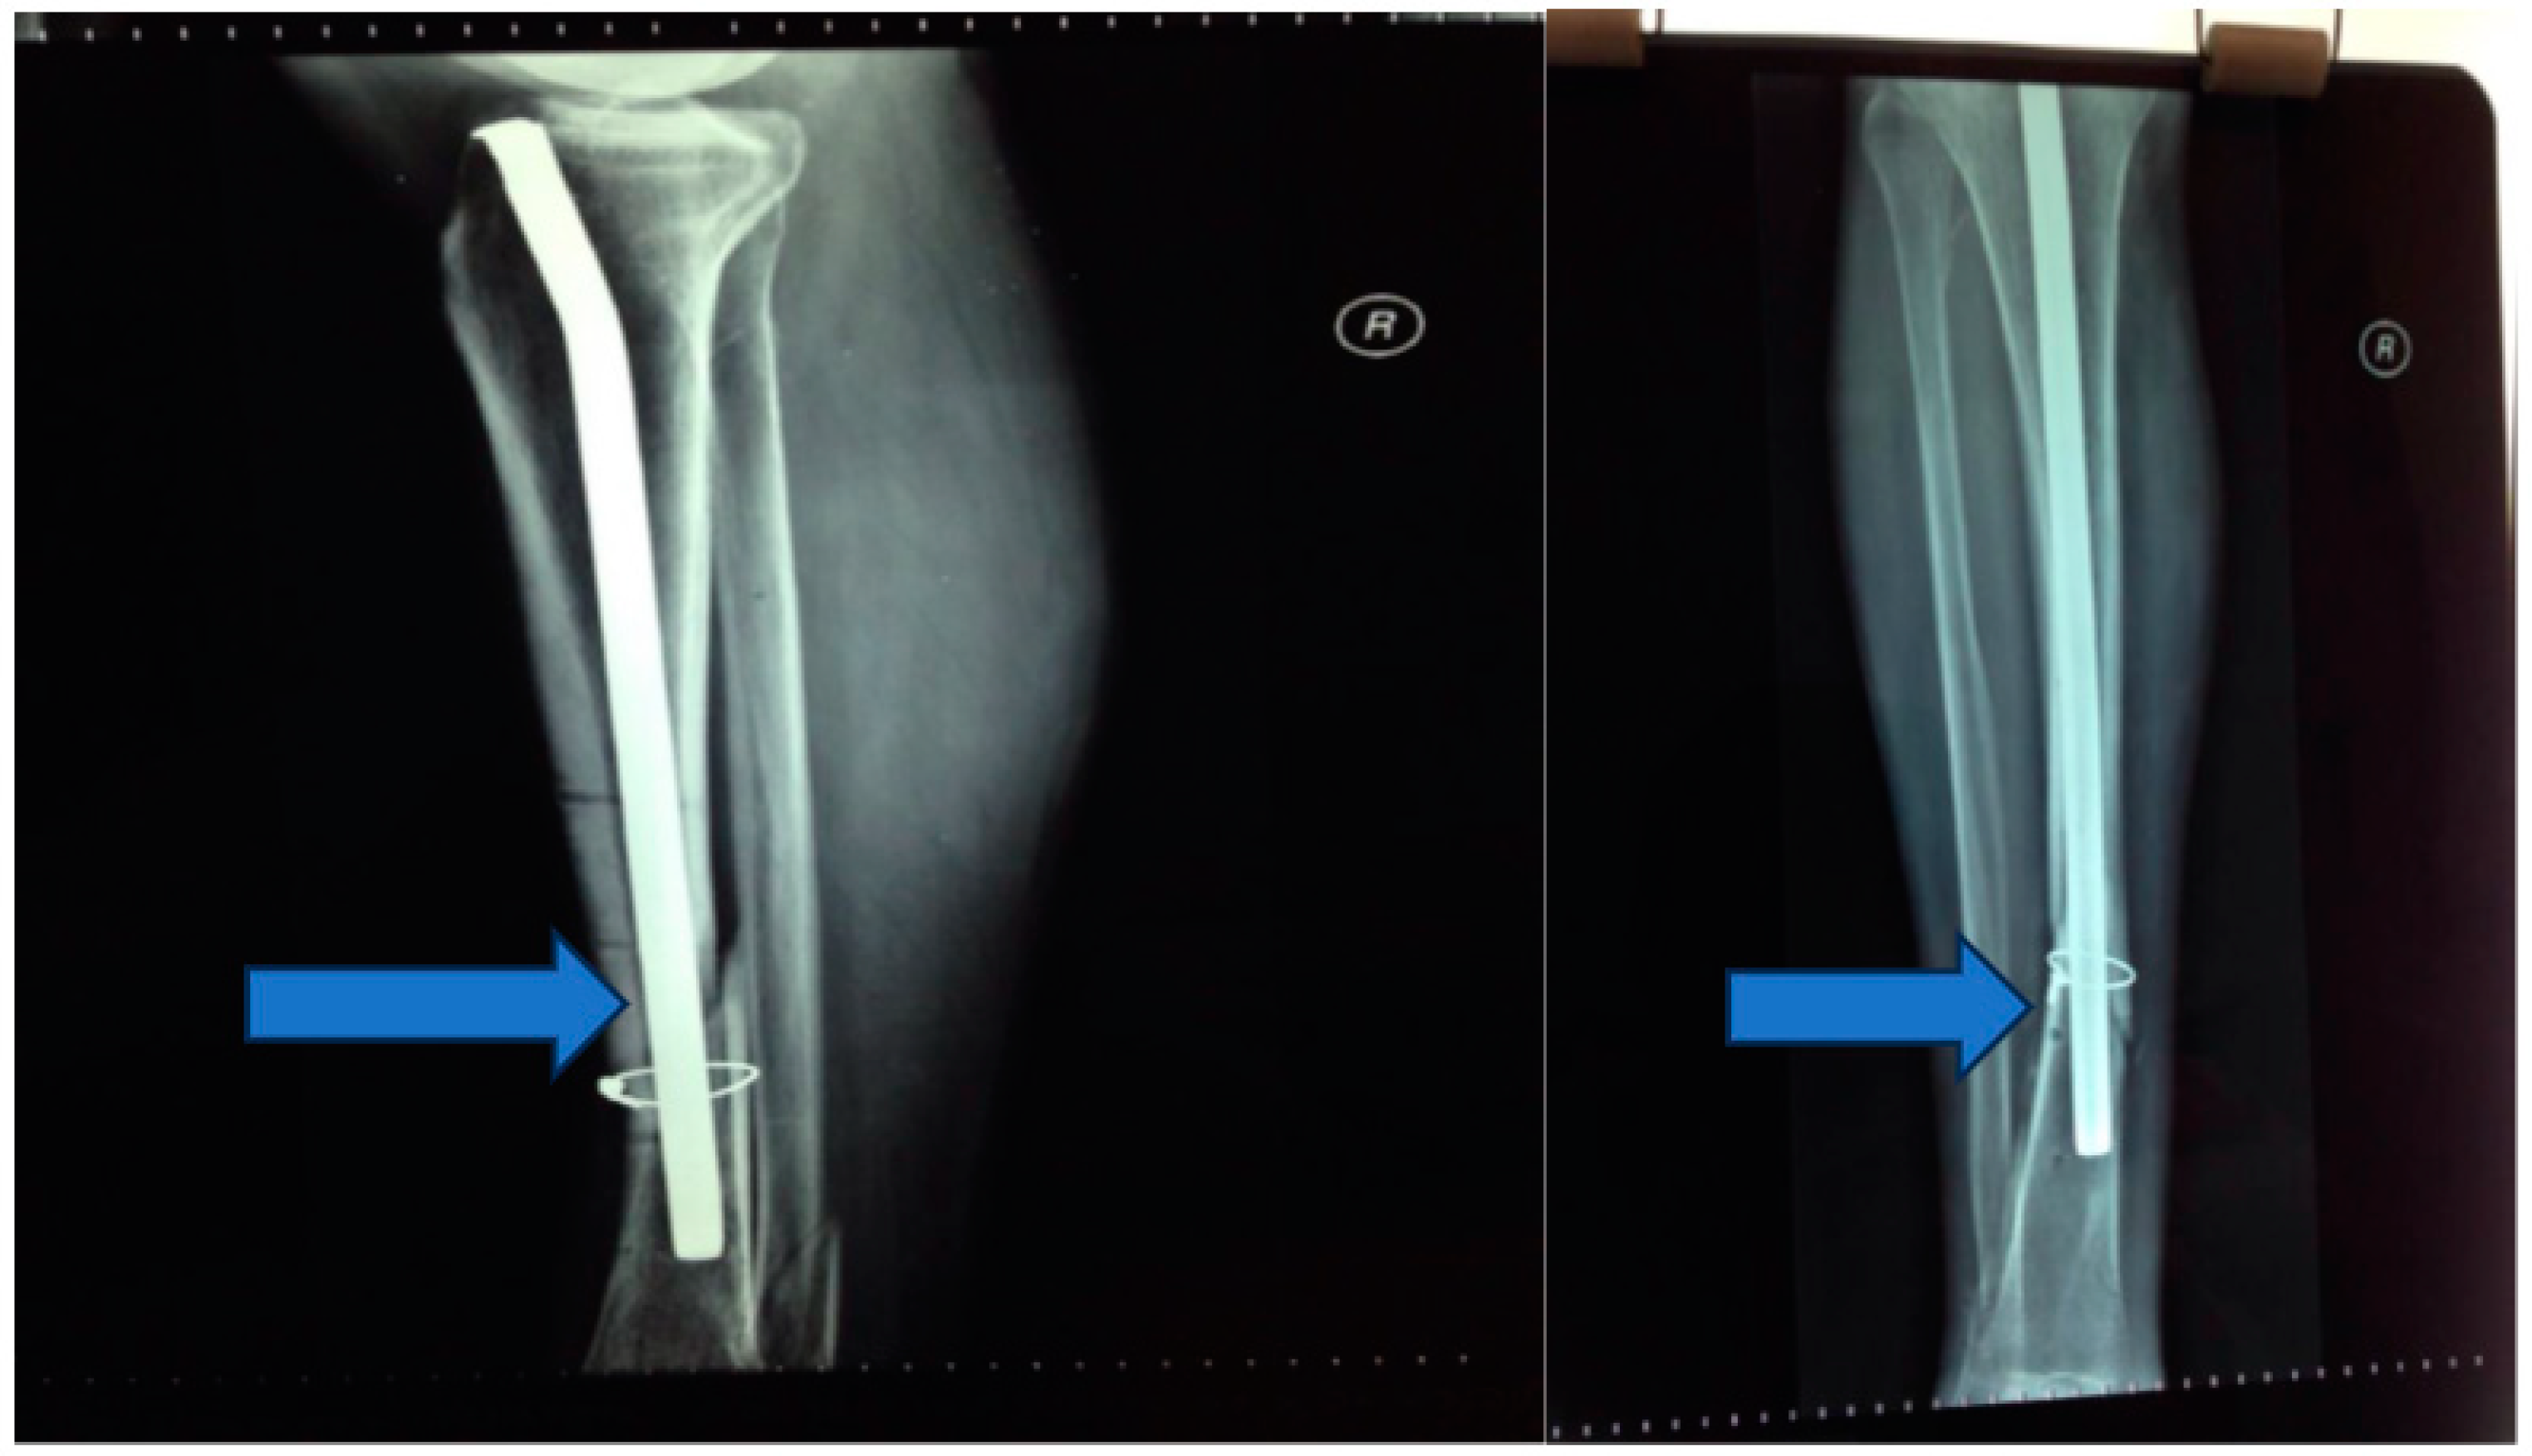

Stage 1: initial stabilization and osteosynthesis (Figure 1).

Objective: To provide immediate stabilization of the open tibial fracture and initiate the process of bone fixation.

Methods: The patient underwent external fixation in the emergency room.

Seven days postinjury, an osteosynthesis procedure was performed, involving the placement of a Kuntscher nail and wire cerclage (Figure 2 and Figure 3).

Figure 1. (A,B) External fixation in the emergency room.

Figure 2. Kuntscher nail and wire cerclage.